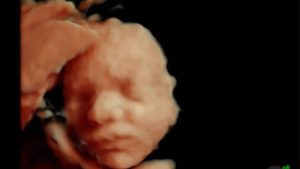

Marnie Simpson’s 4D Scan Experience | Window to the Womb

Window to the Womb Watford opened their doors to former Geordie Shore star Marnie Simpson and her partner Casey Johnson (former X-Factor & Ex-on-the-Beach star). Marnie